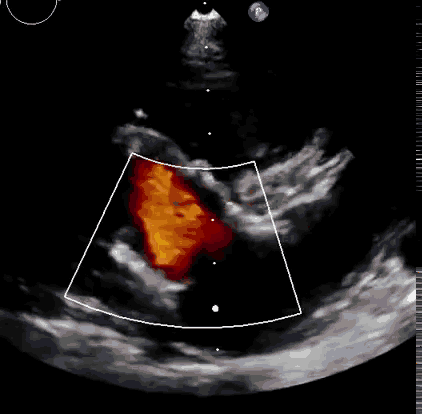

本次臨床前研究經(jīng)右側(cè)頸靜脈置入LuX-Valve Plus輸送系統(tǒng)可調(diào)彎鞘管,在DSA及超聲引導下將人工三尖瓣瓣膜植入到原有三尖瓣位置,利用獨特的錨定技術(shù)將人工瓣膜支架可靠固定在預(yù)定的位置。

上海中山醫(yī)院葛均波院士、錢菊英院長、周達新教授、潘文志教授、潘翠珍教授、李偉教授共同完成此次臨床前研究。術(shù)后葛均波院士對Lux-Valve Plus的器械操作性能給予了高度評價,DSA和超聲影像也顯示出在本次研究中Lux-Valve Plus的安全性和有效性俱佳。